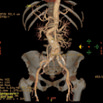

Aorta VR

从外形上显示腹主动脉及其主要分支血管的起源、走形和形态